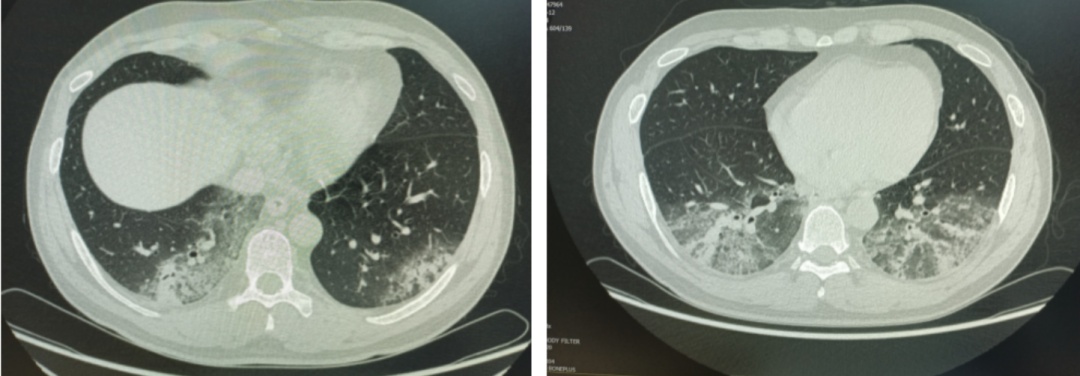

周敏表示,此前也收治因空调久未清洗而感染军团菌的患者。“当时患者自诉感冒后发热、咳嗽、咯痰,自己服用感冒药无效,入院后患者持续发热。”她回忆道。入院检查后发现,患者的肺部存在严重感染,多项感染指标明显升高,最终明确诊断为军团菌肺炎。

在追溯病因的过程中,患者回忆起病前曾在单位附近的篮球运动后,使用了久置未开的空调,随后出现感冒症状并逐渐加重。